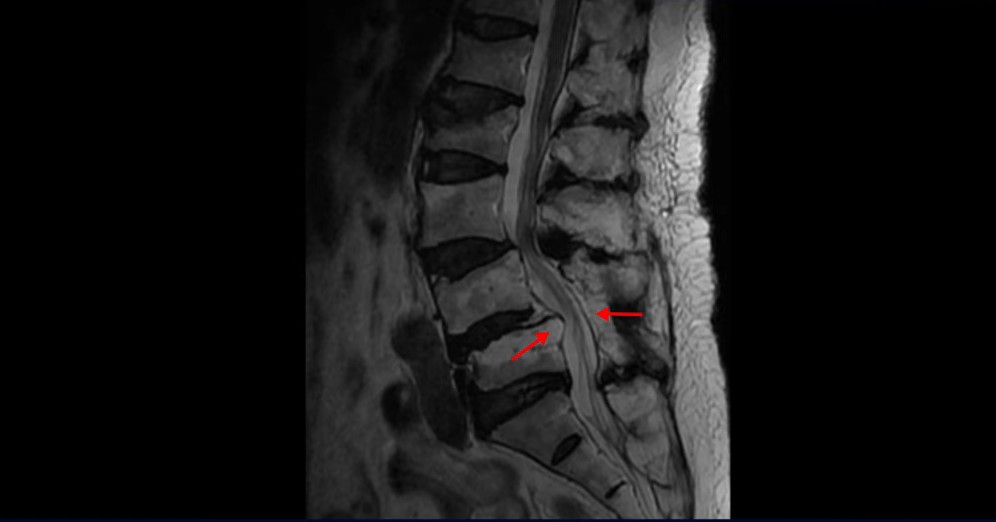

이 환자분은 협착증 수술 예약을 날짜까지 잡아놓고 넘어지면서 압박골절이 발생하고 협착증 증상 즉, 골반과 다리증상이 심하게 악화됩니다. 이분 MRI를 보시면 척추 2번 뼈에는 넘어지면서 생긴 척추압박골절이 보입니다.

3번과 4번 마디에는 황색인대 골화증으로 인한 중심성 협착이 보입니다.

4번과 5번 마디는 전방전위증이 있고 15년 전 허리수술을 받은 적이 있어서 척추 후관절과 후궁을 제거한 흔적들이 보입니다.

또 5번 1번에는 왼쪽 신경가지가 빠져나가는 추간공 즉 신경구멍이 많이 좁아져 있습니다. 이 환자분은 허리통증과 함께 왼쪽 다리 증상이 심하셨는데 이것 때문인 것으로 보입니다.